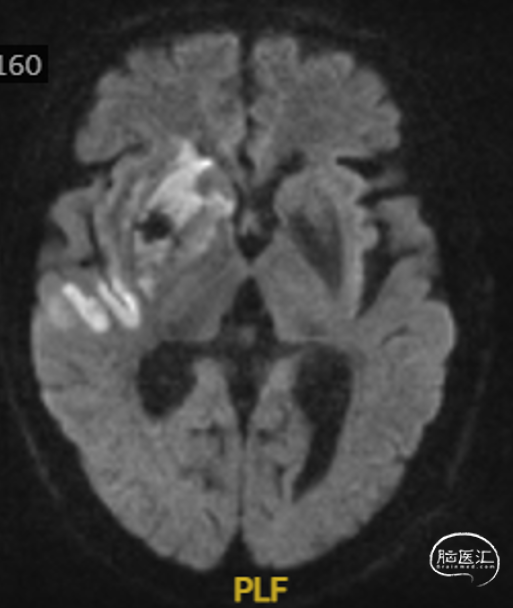

术后MRI